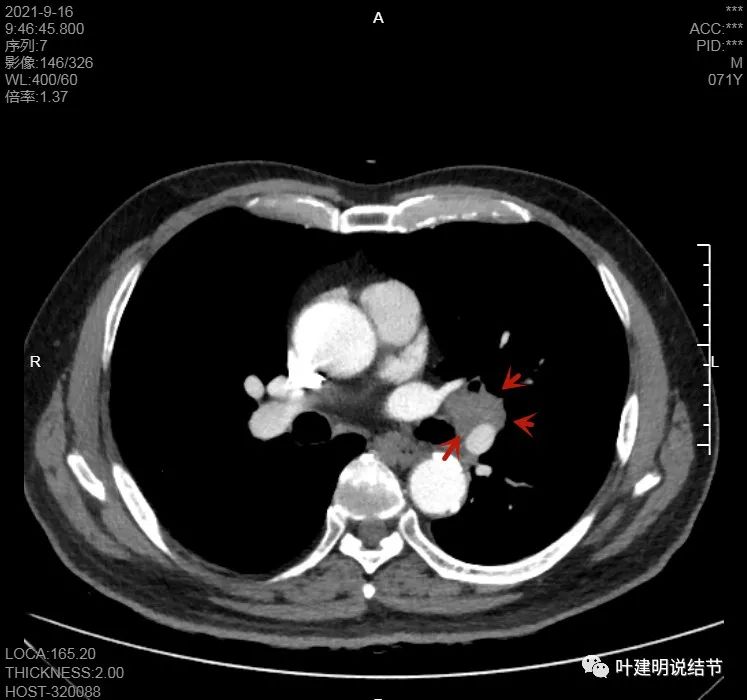

肺门区淋巴结挤压附近肺血管,但似乎示见肿瘤侵犯破坏血管壁

淋巴结巨大,部分包绕肺血管,但仍未见明显侵犯血管壁

肺血管受压明显,气管内壁感觉也是光滑的

以上诸图均示肿大淋巴结挤压肺血管,但未见确切侵犯破坏,支气管内壁也感觉是光滑的,没有肿瘤突向管腔